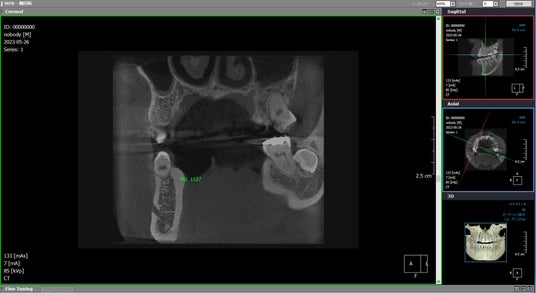

もう一つCBCTの課題を挙げるとすれば、CT値(ハンスフィールド値)に定量性が無いということでしょう。これは、医科用CTと歯科のCBCTの構造的な違い、つまり医科用CTと異なり、CBCTの場合、受け側であるセンサー側にコリメータ―などのグリッドが無いので、どうしても余計なフォトンがセンサーに入射してしまうことが原因と言われています。

PanoACT 3D Upgradeでは、補正技術を用いて【図7】に示すように医科CTのCT値並みの数値が表示されるように開発しましたので、高空間分解能でありながらCT値にもこだわった装置です。

【図7】PanoACT 3D UpgradeのCT値表示機能 ※CT値:緑色の数値